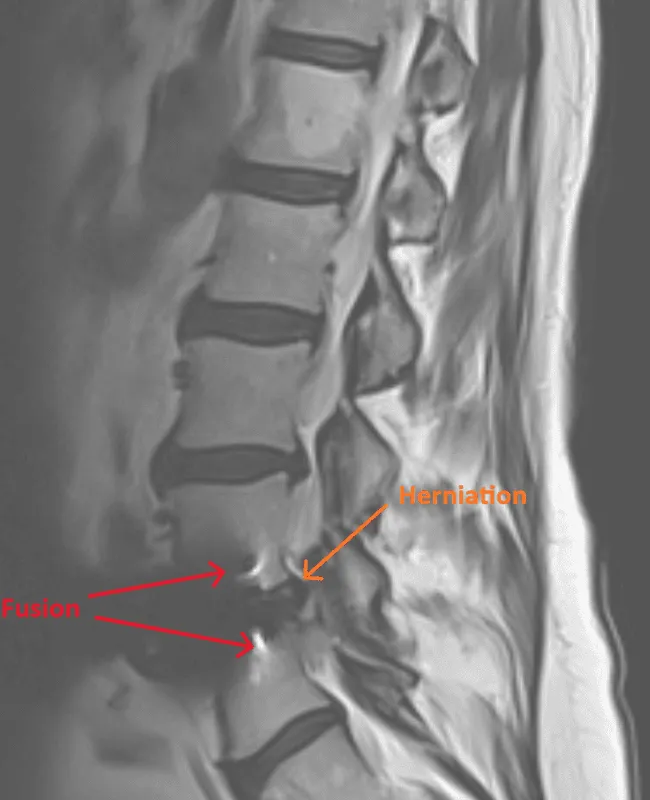

MRI of the spine showing herniation and fusion marked with arrows.

Recurrent Disc Herniation

Disc herniations reoccur at fused or adjacent levels, requiring additional surgery.